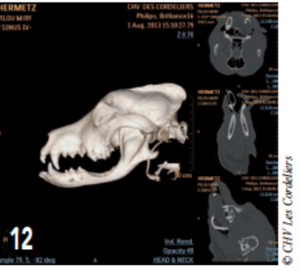

Photo 12 : Reconstruction en 3D du crâne en postopératoire.

L’ostectomie n’ayant pas créé de discontinuité entre la partie articulaire de la mandibule et la symphyse, il n’y a aucune malocclusion.